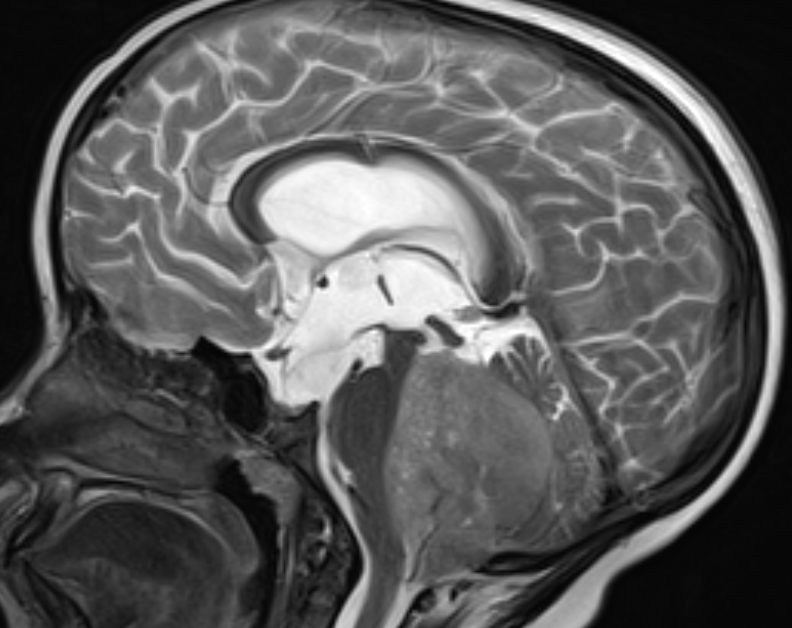

发生于后颅窝的髓母细胞瘤,常见于16岁以下的儿童和青少年,是该年龄段最常见的颅内恶性肿瘤。

事实上答案是非常积极的,通过现在的综合治疗手段,能使75%的患儿活到成年,影响日后好坏的因素,包括发病时患儿的年龄,是否有脊髓的播散,手术切除的程度,以及放化疗的反应等一系列因素。根据肿瘤组织类型的分型,髓母细胞瘤有的好,有的坏,最好的5年生存率能达到100%,而即使是最差的经典型,5年生存率也能达到70%−80%。

1. 定期的随访与观察,在初诊断的1-2年内,要求每3个月到6个月进行一次磁共振的检查,包括全脑和全脊髓的磁共振检查,如果病情没有复发和进展,此后可以延长为每6个月到一年进行一次检查;